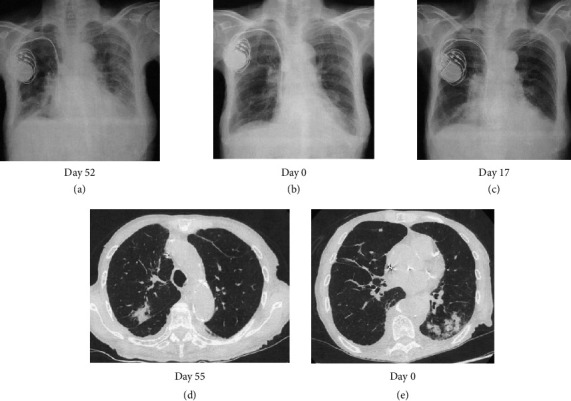

Acquired factor V deficiency (AFVD) is a rare coagulation abnormality associated with infectious diseases, antibiotics, surgery, autoimmune diseases, and malignancy, which causality is difficult to prove. Here, we report a case of a 90-year-old woman who developed melena following antibiotic treatment for pneumonia. She had been on cefepime for bacterial pneumonia for 2 months to 2 weeks prior to her arrival in the emergency room. Upon presentation, she had severe anemia (Hb: 6.7 g/dL) and prolonged PT (74.3 s) and activated partial thromboplastin time (APTT) (161.9 s). Coagulation studies revealed incomplete correction of the APTT in a 1:1 mixing study with normal pooled plasma, factor V activity of 0%, and a factor V inhibitor titer of 13 Bethesda units, confirming the diagnosis of AFVD. Since the antibiotics were not recognized as the cause, the coagulation abnormality worsened after their readministration. The melena subsequently improved with platelet transfusion and administration of tranexamic acid, while prednisolone-resistant coagulation abnormalities improved with cyclosporine A (CsA) treatment. This case shows the importance of avoiding suspected drugs and the effectiveness of CsA as a second-line treatment of AFVD.